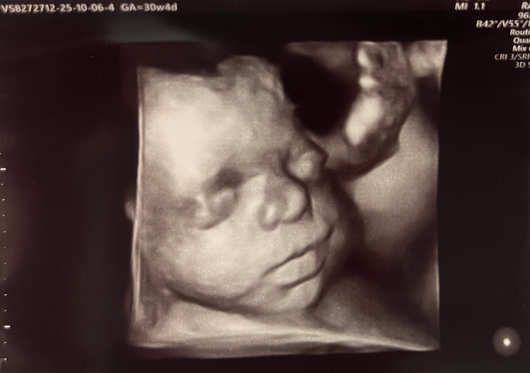

Ecografia 3D

L’ecografia 3D consente di ottenere delle immagini statiche, fisse: delle foto che riproducono le fattezze del feto. La procedura di acquisizione può essere talvolta macchinosa, perché l’acquisizione dei singoli fotogrammi va effettuata muovendo manualmente la sonda. L’ecografia 3D risulta quindi più dispendiosa, in termini di tempo, e può generare incertezza nei risultati: potrebbe essere necessario ripetere l’operazione più volte per ottenere immagini soddisfacenti.

Ecografia 4D

L’ecografia 4D, invece, permette di generare immagini tridimensionali in movimento ed in tempo reale, come se si utilizzasse una videocamera. Questa procedura prevede l’impiego di speciali sonde chiamate “volumetriche”, capaci di acquisire 25–30 fotogrammi al secondo senza movimento della sonda; ne consegue un’immediatezza nella visualizzazione dei particolari tridimensionali fetali.

In definitiva, quindi, l’ecografia 4D e 3D possono essere rispettivamente accostate al video e alla fotografia. La procedura è identica ad una classica ecografia e può essere effettuata sia per via transvaginale che per via sovrapubica. Può essere inoltre eseguita con successo e soddisfazione in qualsiasi periodo della gravidanza: il maggior impatto estetico si otterrà dalla 25.ma settimana in su, quando il feto ha raggiunto una certa dimensione.